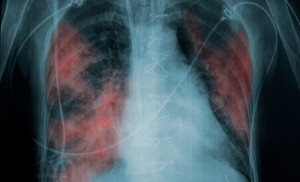

Өкпенің ішінара коллапсы - Пневмоторакc

Частичный коллапс легкого - Пневмоторакс